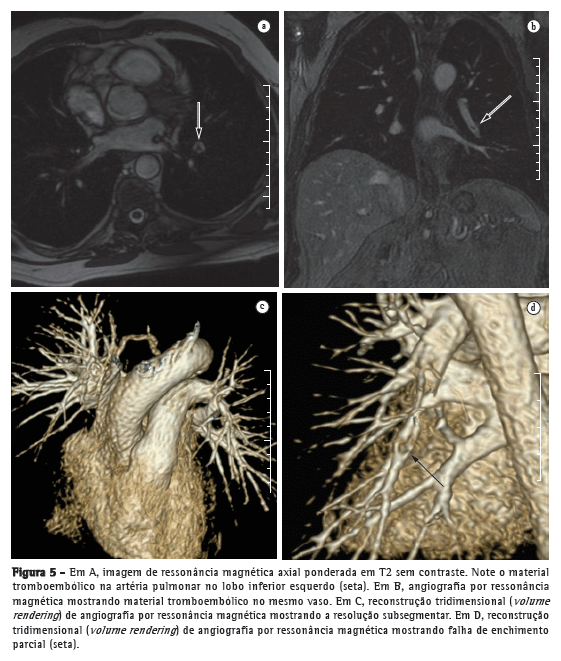

Avanços técnicos substanciais em angio-RM pulmonar foram introduzidos nos últimos anos (Figuras 5 e 6). Novas melhorias estão em andamento; dentre elas, o uso de imagens paralelas, compartilhamento de visão, angiografia do tipo time-resolved echo-shared(17-19) e perfusão pulmonar. Essas técnicas encurtaram o tempo de aquisição da angio-RM, tornaram-na menos suscetível a artefatos de movimento e melhoraram a resolução espacial. Um estudo mostrou que um protocolo combinado de RM (progressão de RM em tempo real para RM de perfusão, e desta para angio-RM) é confiável e sensível, produzindo resultados semelhantes aos obtidos com TC com multidetectores de 16 fileiras.(18)

Em 2003, Stein et al.(20) conduziram uma meta-análise do uso de RM com gadolínio para a visualização de embolia pulmonar aguda. Os autores utilizaram a angiografia pulmonar convencional como padrão de referência. Constataram que a sensibilidade relatada para o procedimento variava consideravelmente (77-100%) e que a especificidade relatada era uniformemente elevada (95-98%).(20) No mais recente dos estudos avaliados naquela meta-análise, Oudkerk et al.(21) mostraram que a sensibilidade da RM com contraste para embolia pulmonar foi de 100% nas artérias centrais e lobares, 84% nas artérias segmentares e apenas 40% nos ramos subsegmentares.

Demonstrou-se recentemente que em casos de suspeita de embolia pulmonar aguda, a RM com um protocolo de última geração com três componentes (sequência true fast imaging with steady-state precession; perfusão e angio-RM com aquisição paralela) é extremamente acurada.(18) A sensibilidade e especificidade relatadas por paciente são de 85% e 98%, respectivamente, para a sequência true fast imaging; 100% e 91% para a sequência de perfusão e 77% e 100% para a angio-RM. A sensibilidade e especificidade relatadas para o protocolo combinado são de 100% e 93%, respectivamente. Embora a RM e a angio-RM sejam específicas, têm baixa sensibilidade, particularmente para embolia pulmonar subsegmentar. No geral, o protocolo combinado de RM revelou-se mais confiável e sensível que a TC com multidetectores de 16 fileiras.(18) Relatou-se que a duração média do exame de RM é de aproximadamente 10 min.(18)